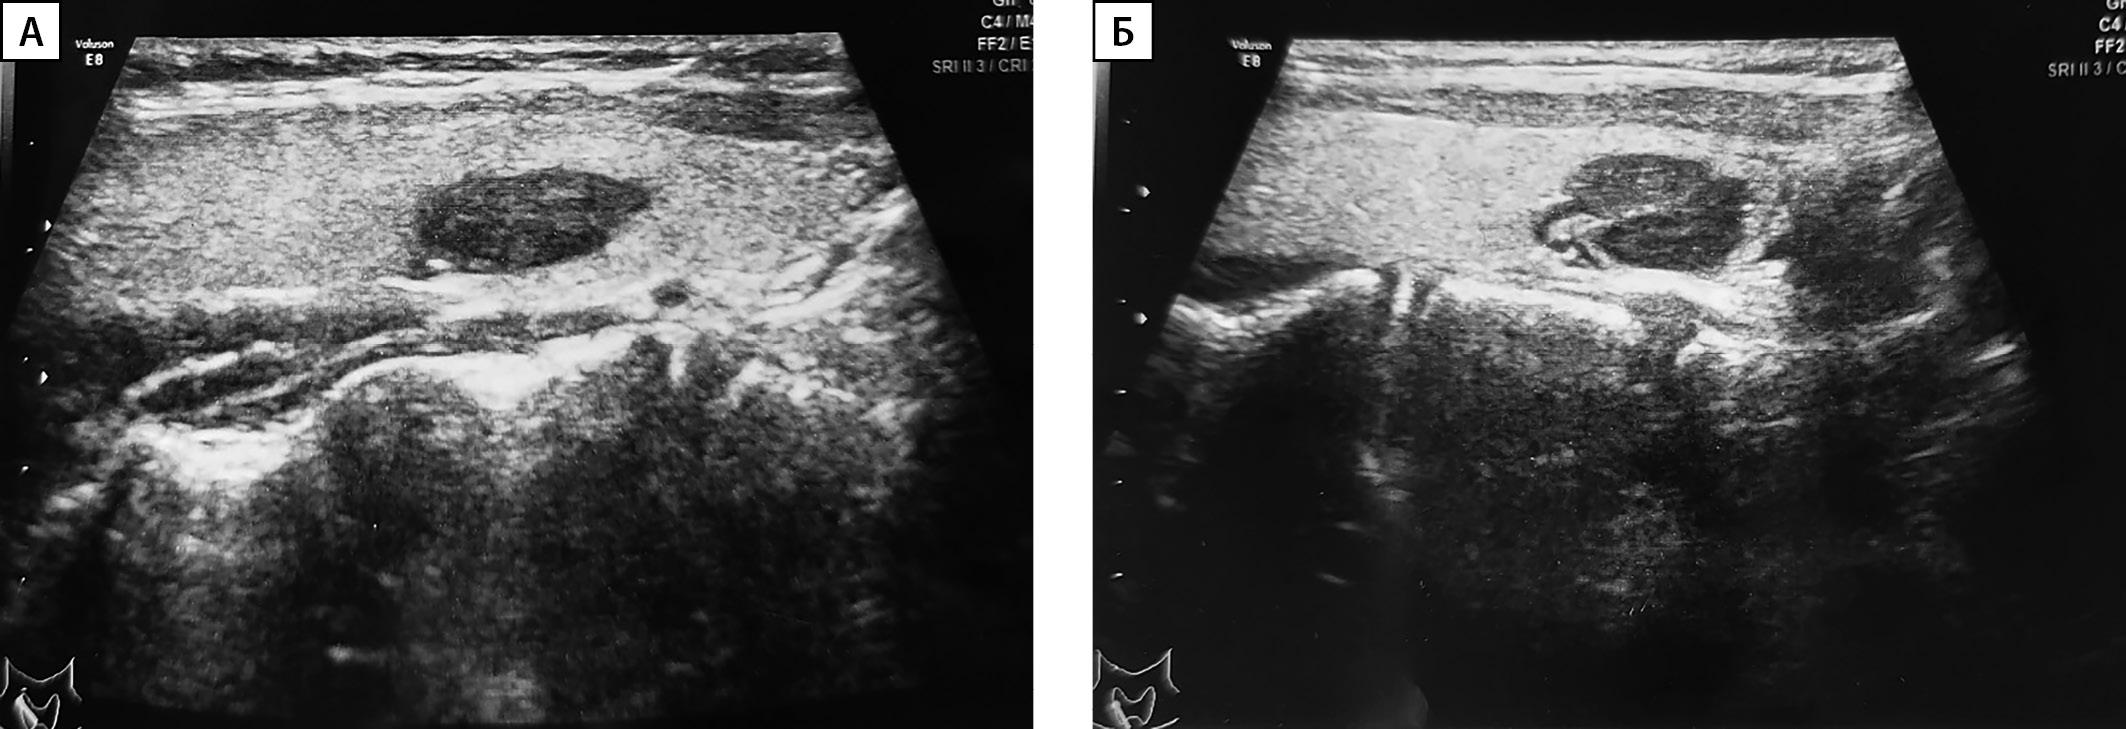

Сцинтиграфия с ОФЭКТ-КТ проведена 33 пациентам, среди них у 26 человек данные сцинтиграфии совпали с результатами УЗИ. У 2 детей по результатам сцинтиграфии выявлены множественные образования ОЩЖ, которые не визуализировались на УЗИ. У 5 пациентов выявлено эктопическое расположение образования ОЩЖ (табл. 2): у 3 пациентов образование было локализовано в ткани щитовидной железы (табл. 2, рис. 2), у 2 — в средостении. У одного из них (пациент №3, рис. 3) данные УЗИ были интерпретированы как образования нижних ОЩЖ, однако при выполнении сцинтиграфии аденома располагалась в области средостения.

Рисунок 2 (А, Б). Ультразвуковое исследование аденом околощитовидных желез,

эктопированных в ткань щитовидной железы.

А — пациент №1; Б — пациент №5.

Ввиду анатомических особенностей топическая диагностика аденом ОЩЖ в ряде случаев может быть затруднена. В проведенном исследовании у 9 пациентов при выполнении УЗИ на амбулаторном этапе по месту жительства образование ОЩЖ было расценено как узел ЩЖ. В своей работе Гостимский А.В. и соавт. отмечали, что часто УЗИ является неинформативным для определения точной локализации образований ОЩЖ [3]. Особую трудность диагностики представляют эктопические образования ОЩЖ. По данным литературы, распространенность эктопий ОЩЖ в детской популяции варьирует от 5 до 26% [26]. Наиболее частыми локализациями являются паренхима тимуса и ткань ЩЖ, реже встречается эктопия в пространстве около пищевода и средостения [27]. В настоящем исследовании эктопия ОЩЖ отмечалась в ткани ЩЖ (n=3), в области средостения (n=1) и паренхиме тимуса (n=1).